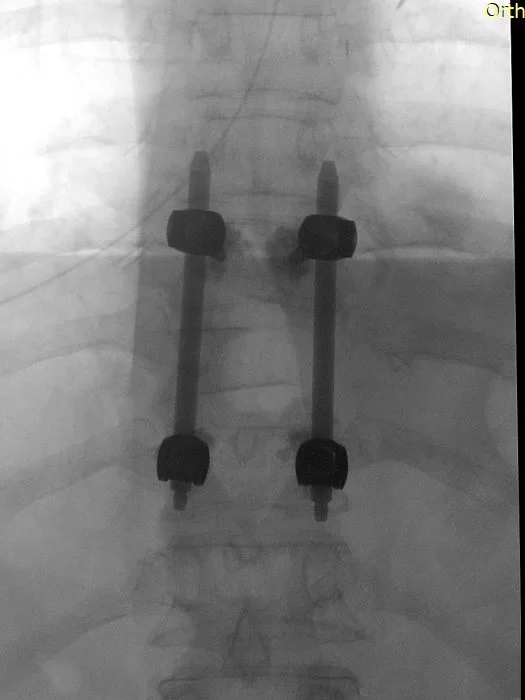

Διενεργήθη αποσυμπίεση του νωτιαίου μυελού μέσω πεταλεκτομίας και αφαίρεσης του ενδοκαναλικού τμήματος του όγκου και στη συνέχεια διαδερμική σπονδυλοδεσία με έγχυση οστικού τσιμέντου στα σπονδυλικά σώματα Θ9-Θ11

Στο συγκεκριμένο περιστατικό συνδυάστηκαν η ανοιχτή μέθοδος της πεταλεκτομίας για την αφαίρεση του ενδοκαναλικού τμήματος του όγκου και την αποσυμπίεση του νωτιαίου μυελού, με τη διαδερμική τεχνική της σπονδυλοδεσίας. Οι βίδες τοποθετήθηκαν με τη βοήθεια νευροπλοηγού το οποίο δίνει στο χειρουργό τη βεβαιότητα της απόλυτης ακρίβειας. Η διαδερμική τοποθέτηση των βιδών κράτησε την τομή μικρή, μειώνοντας σημαντικά τον μετεγχειρητικό πόνο και τον κίνδυνο φλεγμονής, επιτρέποντας στον ασθενή την άμεση κινητοποίηση και έξοδο από το νοσοκομείο. Η ενίσχυση των σπονδυλικών σωμάτων με οστικό τσιμέντο είχε πολλαπλό ρόλο: αφενός βοηθά στη σταθερότητα της σπονδυλοδεσίας (επιτρέποντας μας να έχουμε καλή στήριξη με “μικρή” σπονδυλοδεσία), αφετέρου προσέφερε σταθερότητα στον Θ9 σπόνδυλο ο οποίος είχε προσβληθεί από νόσο.